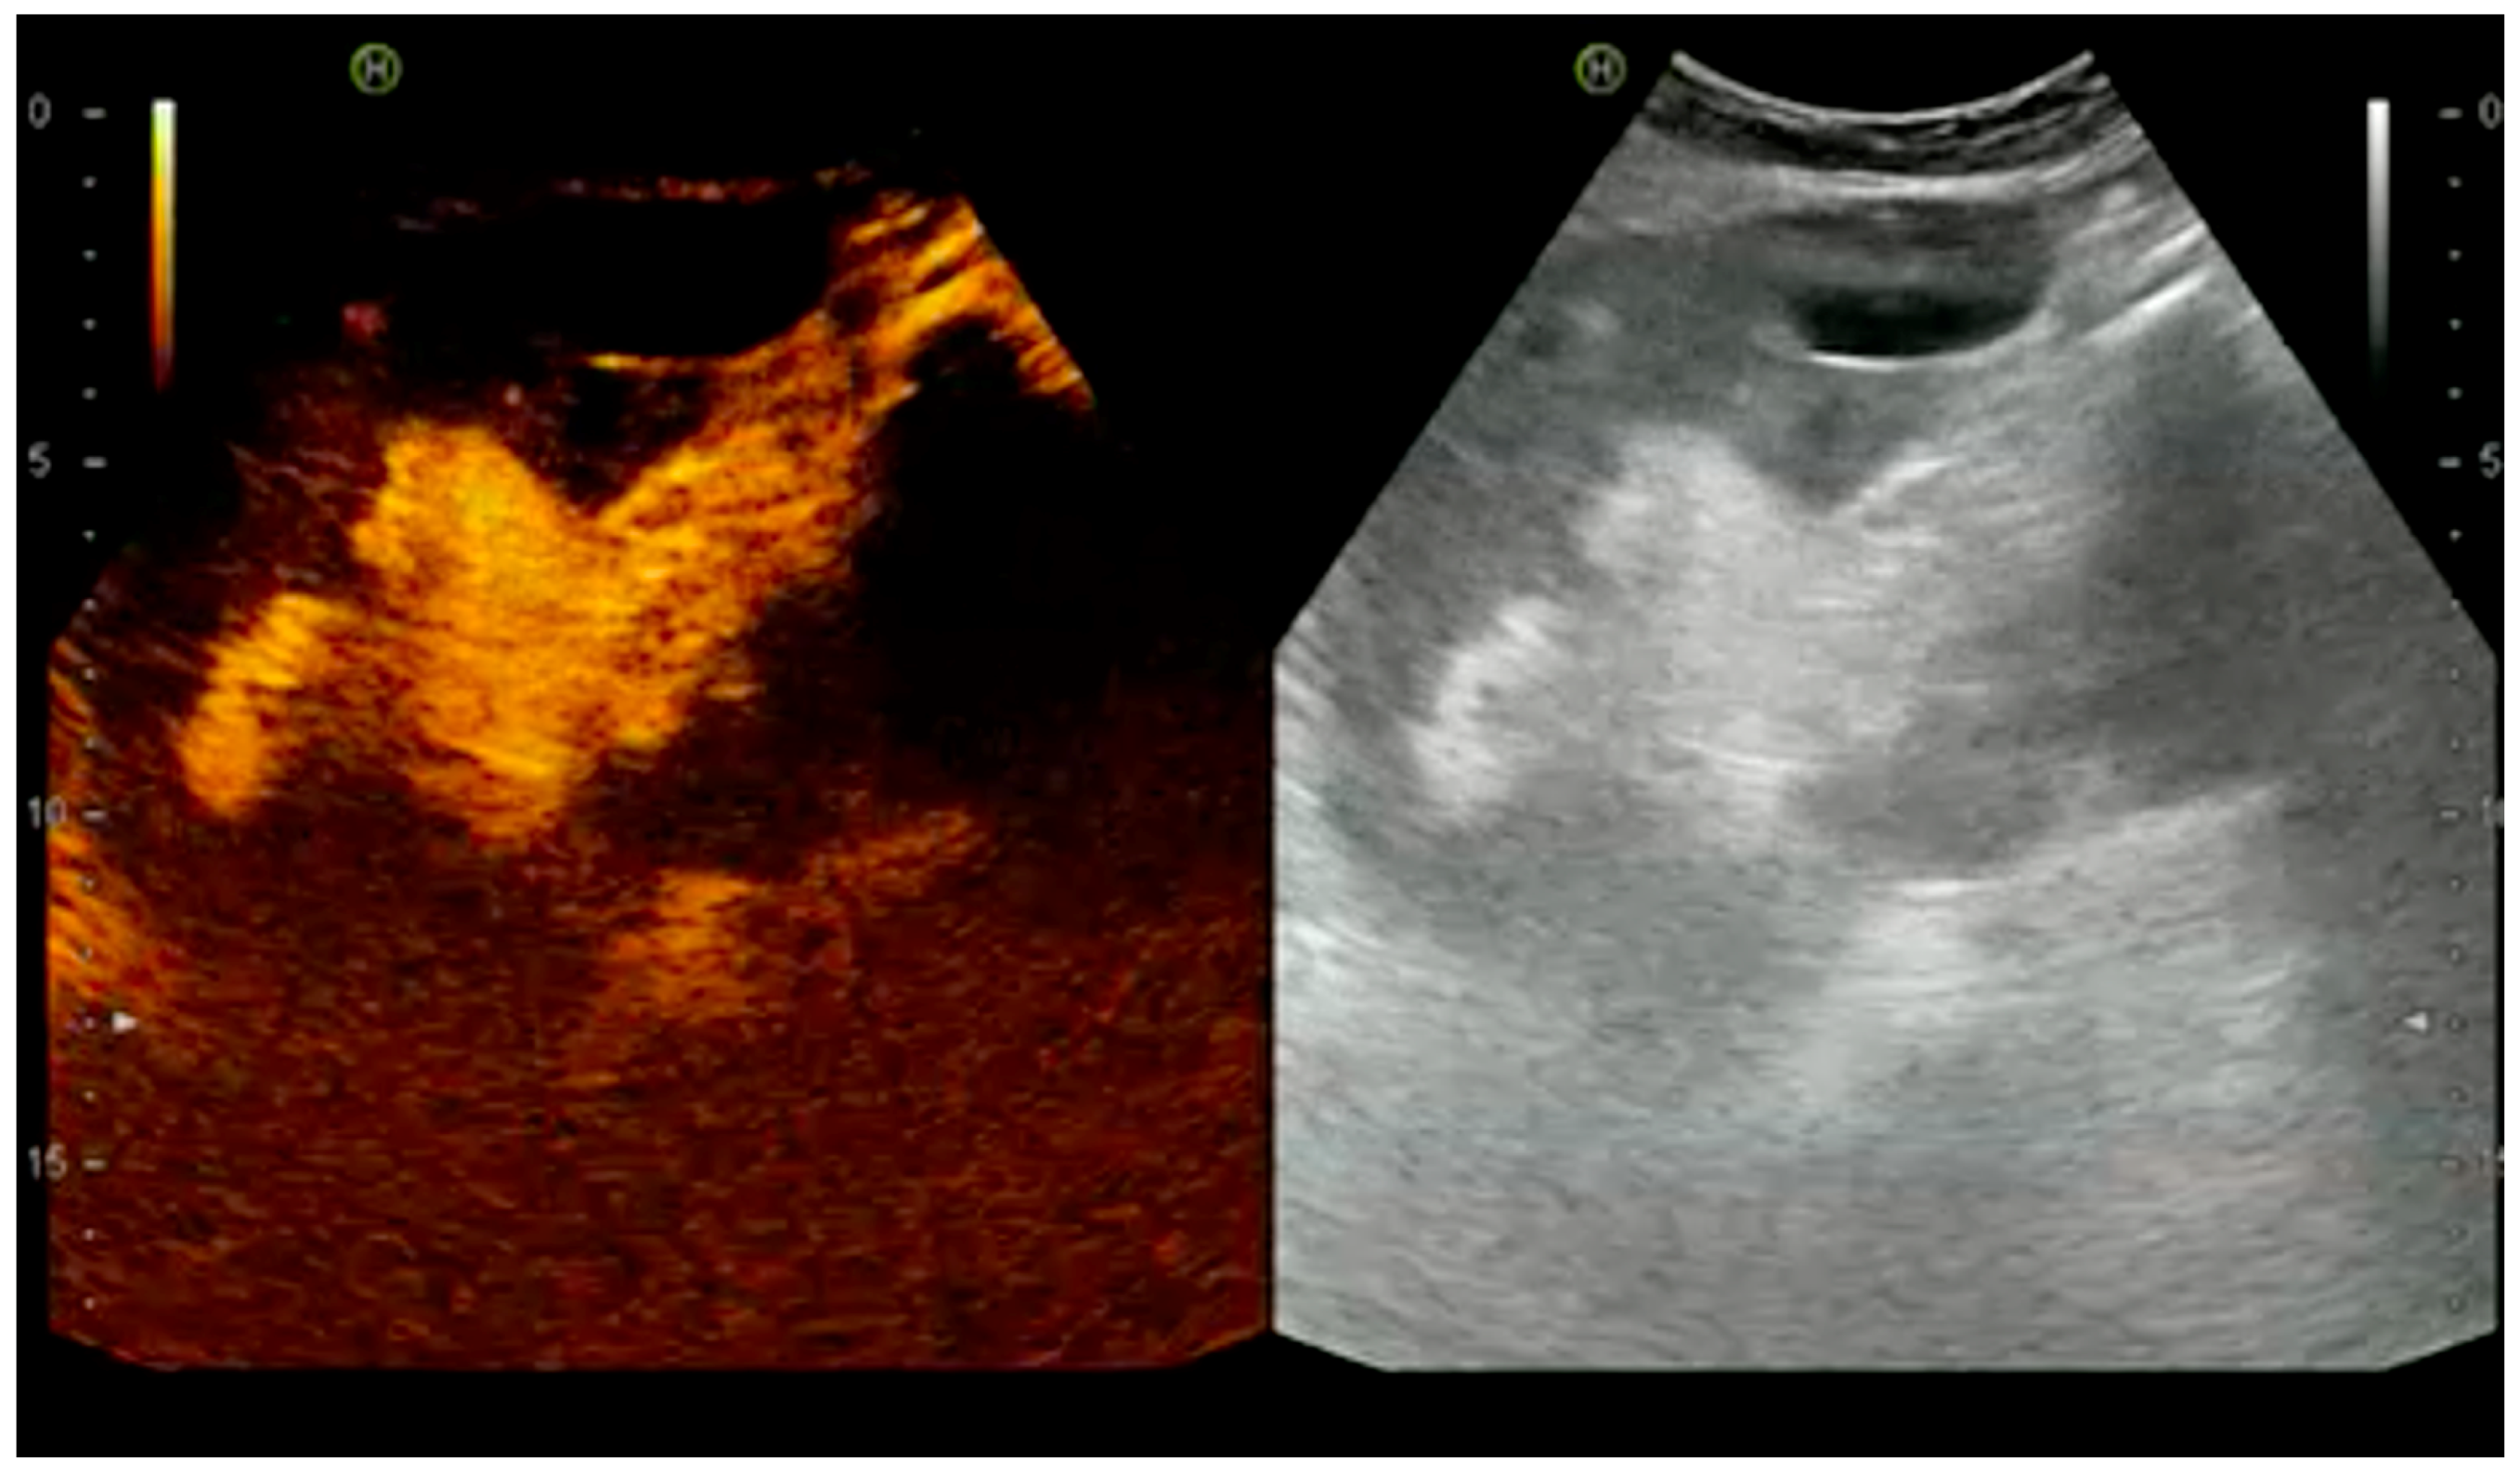

4.1.1. Arterial Thrombosis